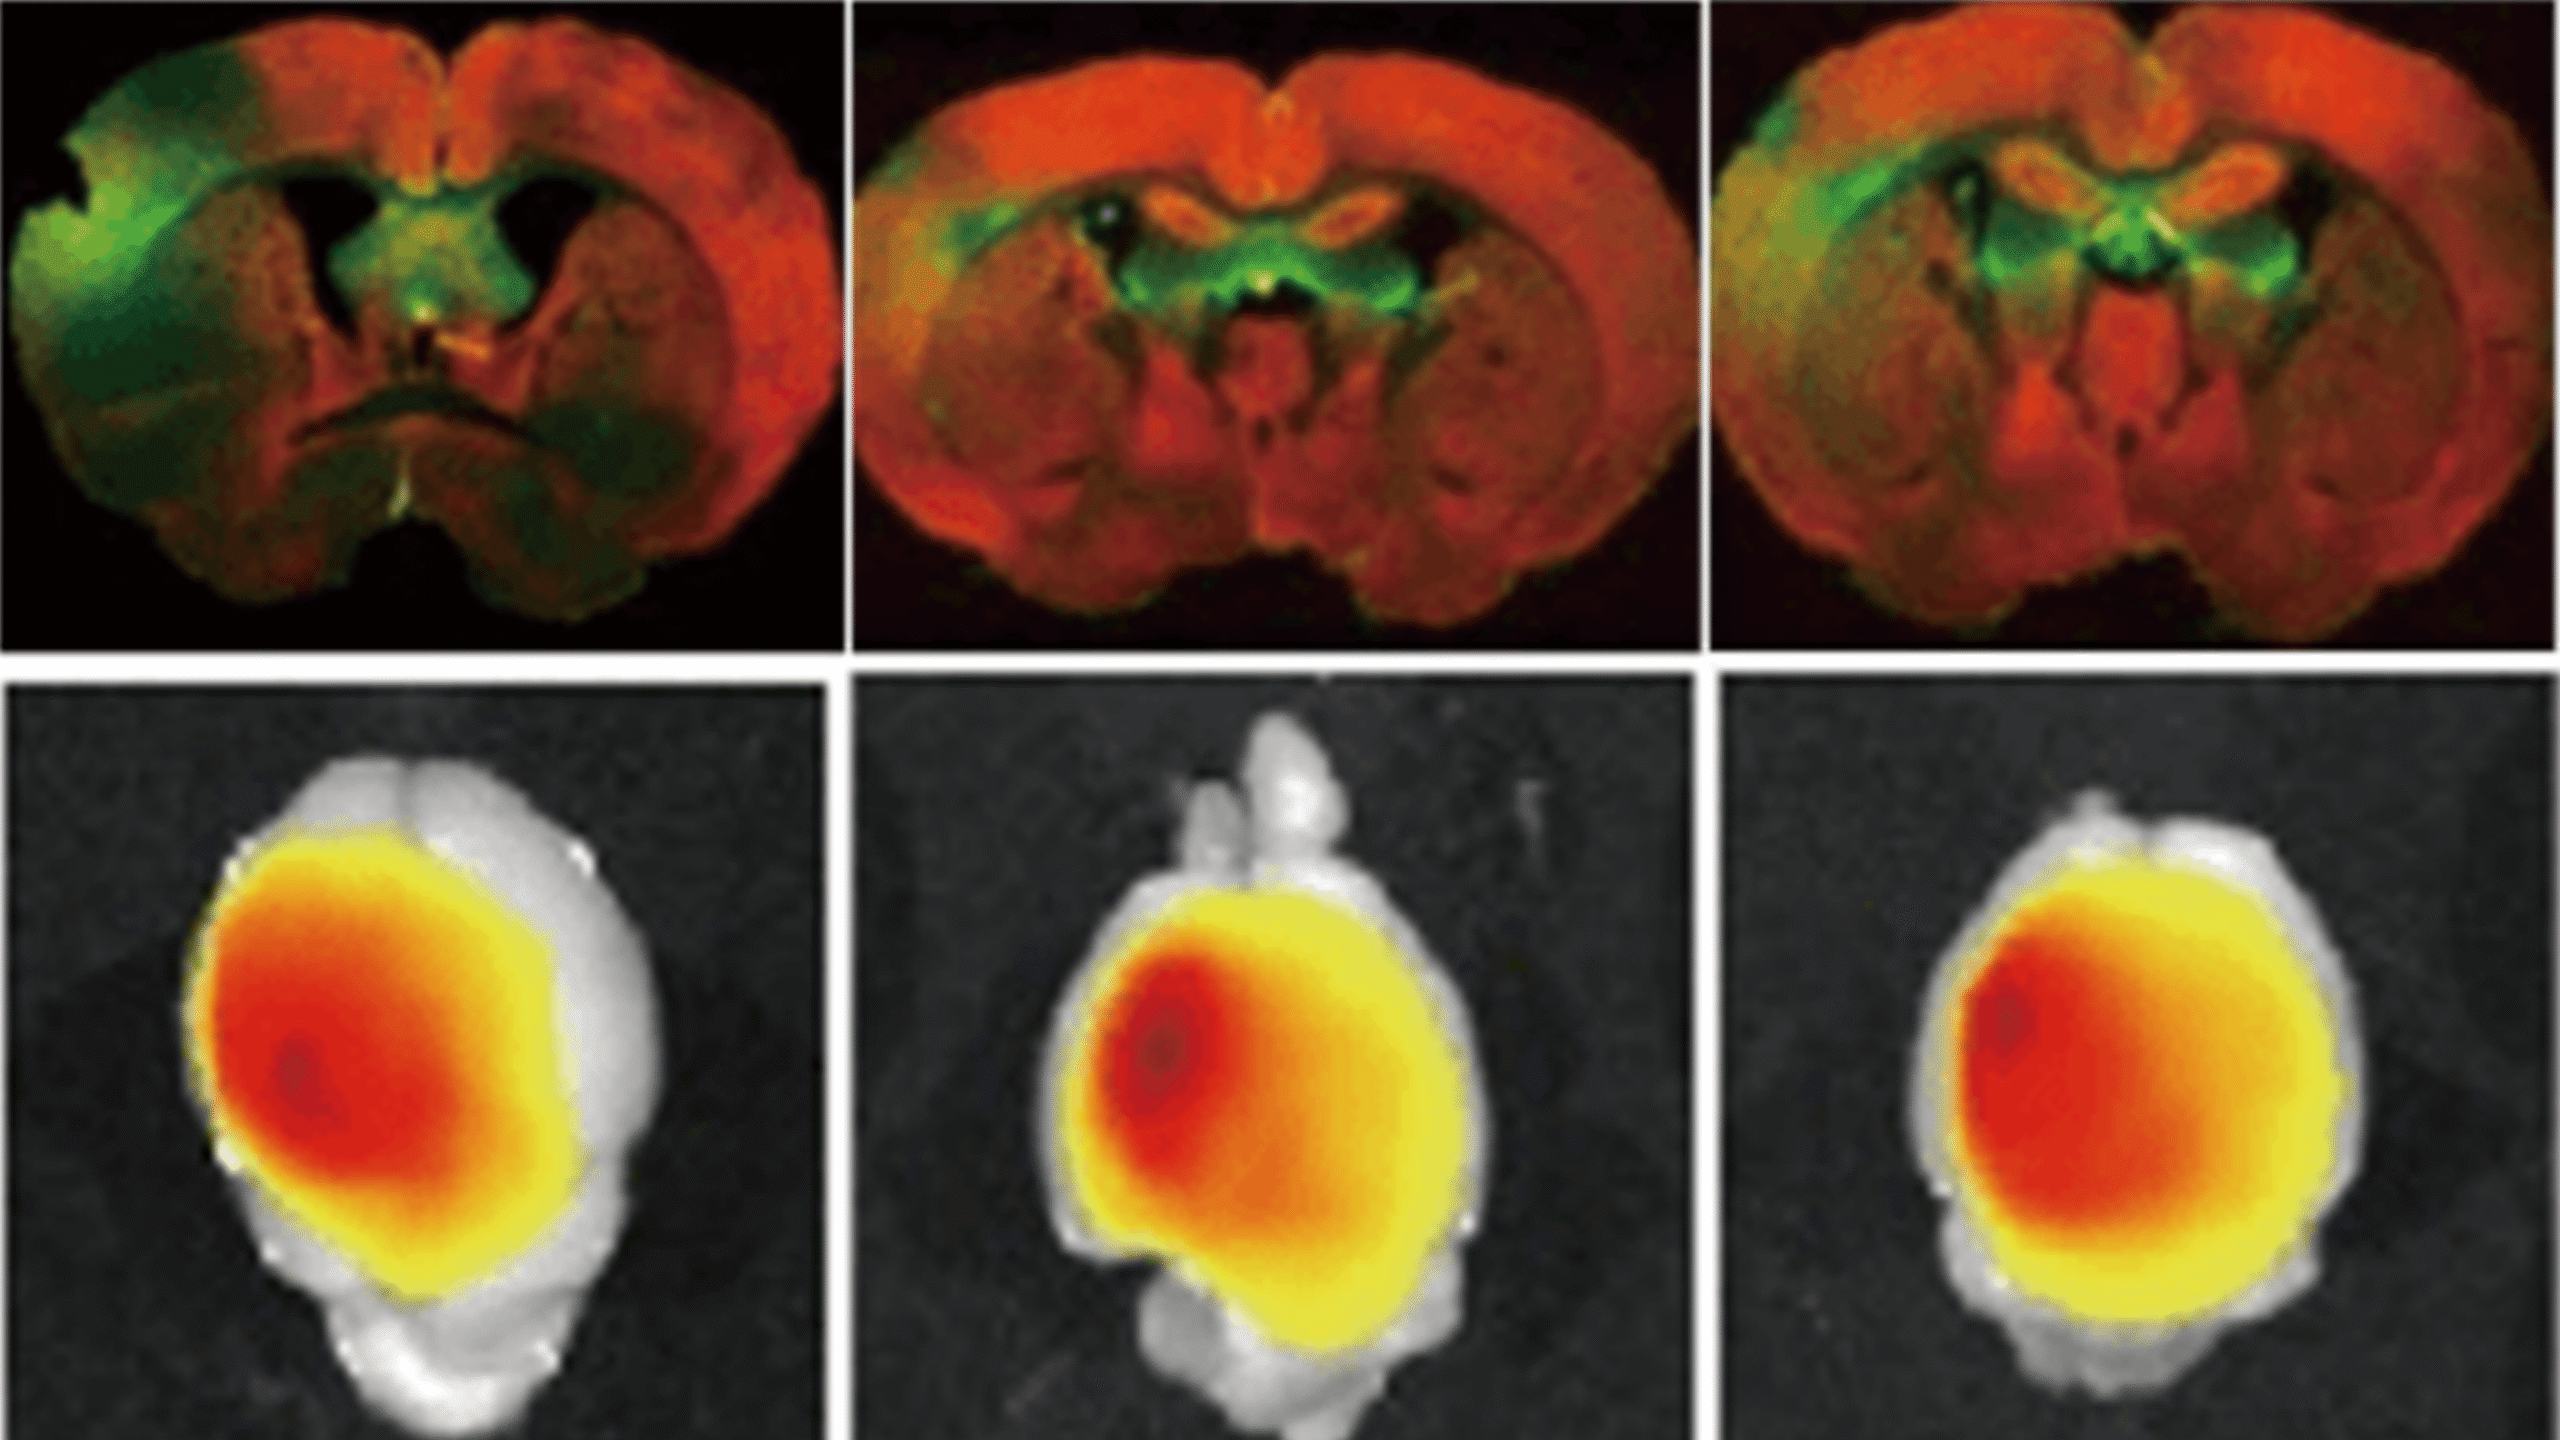

创新构建吸入式 RNA 递送系统实现呼吸疾病治疗机制突破:针对 LNP 雾化后粒径增大、 包封率下降及难以突破黏液屏障等难题,通过脂质结构、制剂创新和制备工艺的多维协同优化,构建兼具优异的雾化稳定性、气动性能与黏液穿透性能的吸入式递送系统,在多种呼吸系统疾病模型中展现出高效的基因调控和显著的治疗效果。

模块化脂质共组装策略实现靶向核酸递送及重大疾病治疗机制创新:提出“模块化分子组装”策略,设计具备靶向功能的脂质模块, 组装构建可高效定向递送至肝星状细胞、巨噬细胞、小胶质细胞等细胞的核酸载体;首次提出“正反馈增效”靶向递送机制,并在心脑血管、肝代谢等疾病动物模型中展现出显著的治疗效果,为重大疾病治疗开辟新路径。